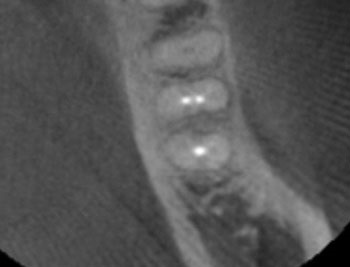

Case 2: A U-shaped lesion

Tooth #30 presented with a diagnosis of previously treated and symptomatic apical periodontitis. The radiographic lesion encompassed both sides of the mesial root, forming a U-shaped lesion. Periodontal probing extended to the apex. The prior endodontic root preparations were relatively large, compared with the root canals on the patient’s other untreated teeth. Because the bone loss associated with a U-shaped lesion encompasses both sides of a root, it might be considered even more indicative of a potential VRF than a J-shaped lesion.

This patient had been examined by an endodontist, who recommended extraction because of a VRF. Although multiple risk factors were identified, no fracture was seen upon access, and this tooth was successfully retained through nonsurgical retreatment.

Fig. 7: Recall PA.

Fig. 8: Recall CBCT.